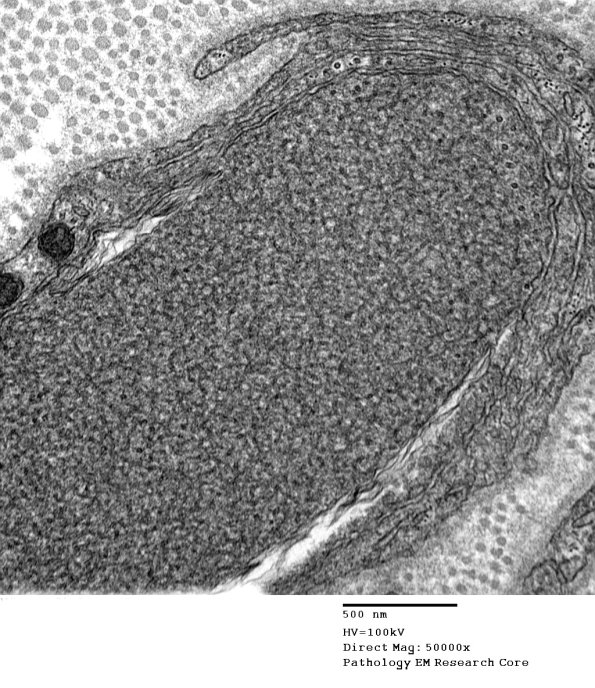

Higher magnification of image #1B6A. (electron micrograph)